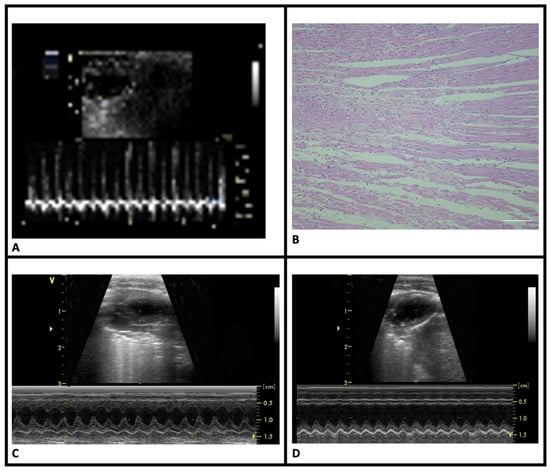

Clinical verification of MI: Following ligation of the LAD, the myocardium distal to the ligation site turned purple or pale, and the heartbeat weakened with visible congestion of the left auricle. MI was confirmed via an ECG, which showed ST elevation (Figure 2A).

Figure 2. Clinical and histopathological features of myocardial infarction. (A) ST-segment elevation on electrocardiogram tracings of MI-induced groups. (B) Coagulative necrosis in the HE-stained sections of MI-induced animals. (C) Normal wall motion of the sham-control group in M-mode echocardiography images. (D) Significant akinesia in the anterior wall of the MI-control group in M-mode echocardiography images (HE, scale bar = 20 μm).

Histopathological verification of MI: HE staining revealed pathological changes in LV consistent with acute MI. Compared to the sham-control group, the MI groups displayed signs of acute infarction, including eosinophilia, karyolysis, leukocyte infiltration, and disorganization of muscle fibers. Infarct regions were primarily located in the anterolateral LV, extending from the sub-endocardial to endocardial area (Figure 2B). There were no statistically significant differences in infarct sizes between the MI groups (Table 1).

Cardiac functions: Echocardiographic assessments of LV geometry and function are shown in Table 1. Compared to the sham-control group, MI-control rats exhibited significant LV structural changes, including thickening of the remote non-infarct myocardial wall (Figure 2C,D). Functional abnormalities characterized by decreased ejection fraction (EF) consistent with structural changes were observed in this group. Nebivolol treatment preserved both LV structure and function in the MI-neb1 and MI-neb2 groups.